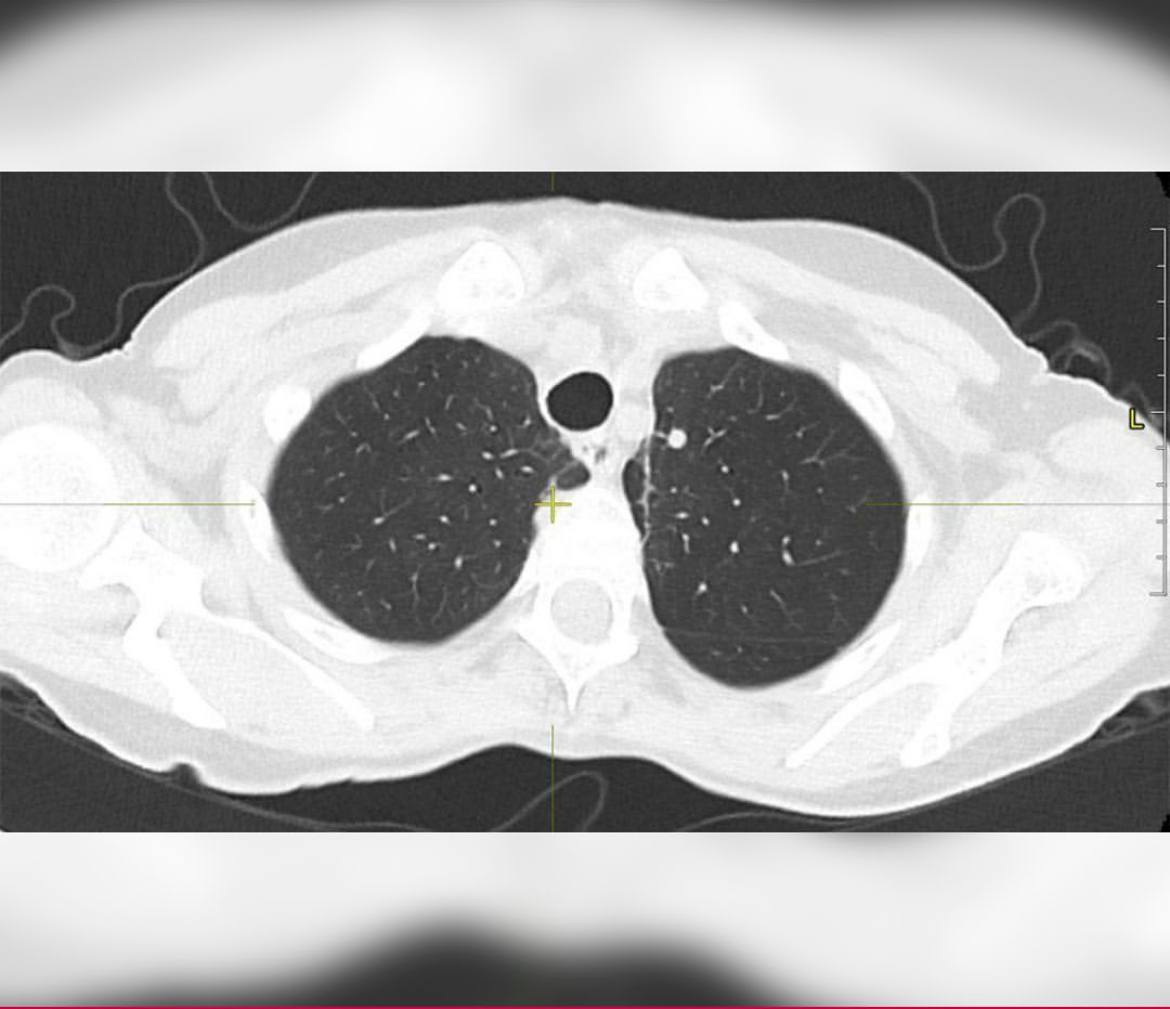

Диагностика показала наличие метастатических процессов с первичным очагом в грудной клетке. Это образование и было причиной болей. Результаты биопсии подтвердили лейомиосаркому.